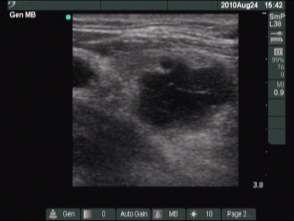

First session (first row of images):

Clinical presentation: the patient told us that her persistent cough lasting for several month have stopped after removal of cystic fluid for five or six weeks. Thereafter this complaint recurred.

Palpation: no abnormality.

Ultrasonography: the cysts has recurred.

We offered ethanol sclerotherapy. We aspirated 4 mL watery fluid and administered 1.5 mL ethanol.